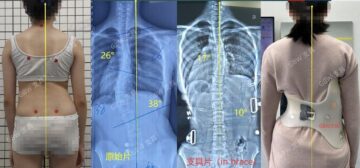

مارس 28, 2026 الحياة بعد حزام اعوجاج العمود الفقري: هل يعود الظهر طبيعيًا؟ وماذا بعد انتهاء العلاج؟… scoliosis, اعوجاج العمود الفقري, الجنف لا يوجد تعليق 62 المشاهدات الحياة بعد حزام اعوجاج العمود الفقري: هل يعود الظهر طبيعيًا؟ وماذا بعد انتهاء العلاج؟ عندما يقترب الطفل أو المراهق من إنهاء فترة استخدام حزام اعوجاج العمود الفقري، يبدأ الأهل في طرح سؤال مهم ومقلق